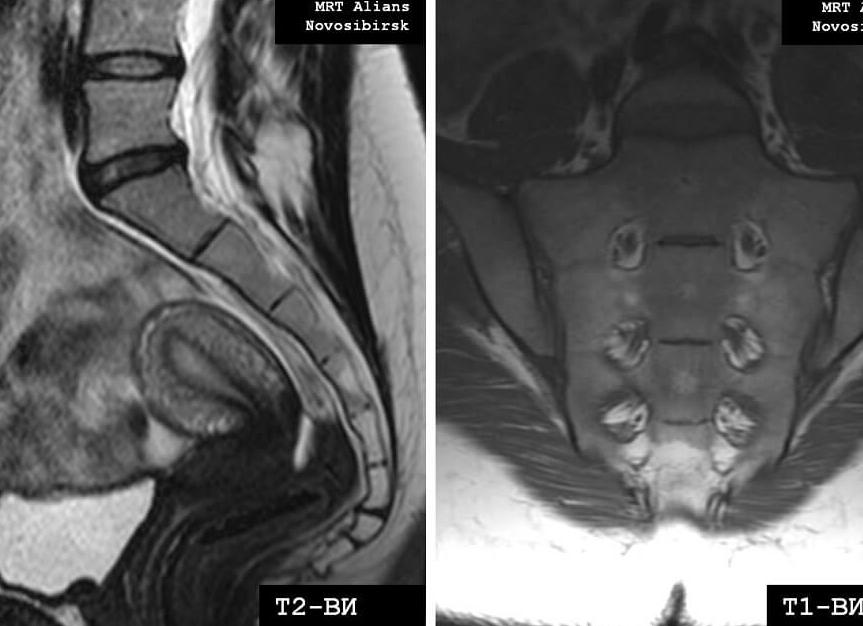

Пациент ложится на стол томографа, в области таза закрепляется специальная радиочастотная катушка. Далее пациент перемещается в апертуру аппарата, где и происходит сканирование, которое длится от 20 до 40 минут в зависимости от типа и мощности томографа. В протокол сканирования входят МРТ пояснично-крестцового отдела позвоночника, МРТ крестцово-копчикового отдела позвоночника, а также исследование органов малого таза по показаниям.

Именно поэтому прибегают к МР- томографии крестцового отдела позвоночника. Различные режимы сканирования позволяют точно выявить любую патологию, а также сделать трехмерную реконструкцию костей.

На полученных снимках позвоночника хорошо визуализируются:

- все поясничные позвонки и копчиковые кости;

- межпозвонковые диски;

- спинной мозг;

- нервные сплетения («конский хвост»);

- мягкие ткани.

Магнитно-резонансная томография — МРТ копчика является отличным методом диагностики заболеваний и патологических изменений мягкотканых структур, хрящей, межпозвонковых дисков и костного мозга. Высокая чувствительность и тканевая контрастность позволяют при МРТ копчика выявить даже самые минимальные изменения. МРТ копчика или МРТ копчикового отдела позвоночника поможет визуализировать посттравматические изменения позвонков, крестцово-копчикового синхондроза, опухоли спинномозговых корешков, оценить структуру окружающих мышц и связок.